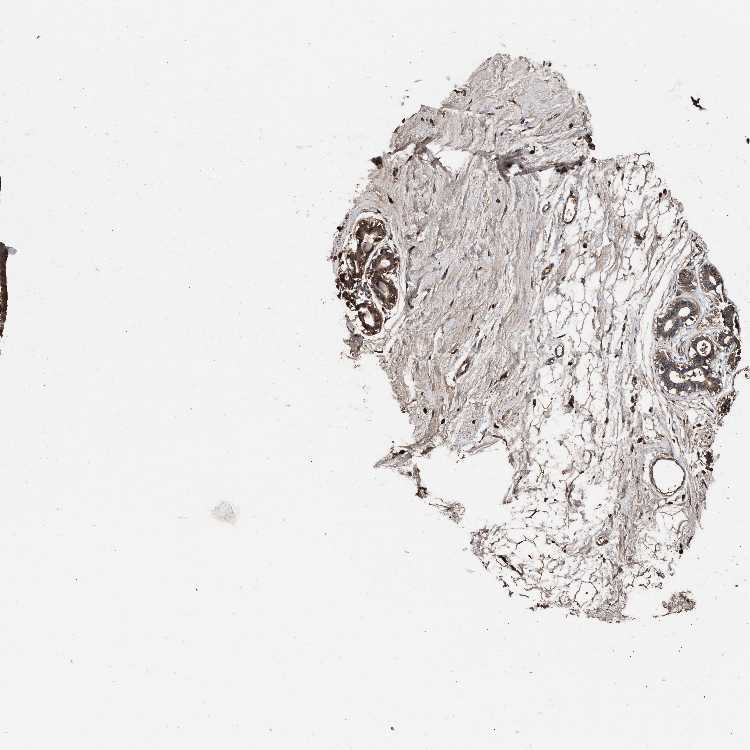

BREAST - Antibody stainingi

Antibody staining in the annotated cell types in the current human tissue is reported as not detected, low, medium, or high, based on conventional immunohistochemistry profiling in selected tissues. This score is based on the combination of the staining intensity and fraction of stained cells.

Each image is clickable and will lead to virtual microscopy that enables deeper exploration of all samples and also displays staining intensity scores, fraction scores and subcellular localization as well as patient and tissue information for each sample.

Antibody HPA021176Antibody HPA021177Antibody HPA027736

Adipocytes MediumMediumNot detected

Glandular cells HighHighNot detected

Myoepithelial cells HighMediumNot detected